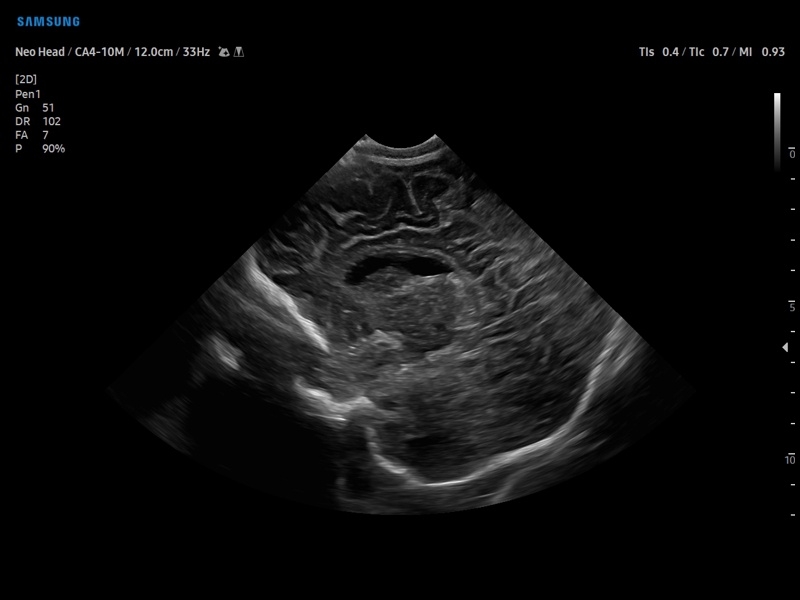

Ультразвуковой сканер V8-RUS является экспертным классом (премиальный уровень) и производится компанией Samsung Medison. Сканер V8 обеспечивает превосходное качество изображения благодаря использованию технологии Crystal Architecture™, которая включает в себя передовое аппаратное обеспечение, монокристальную технологию изготовления датчиков и сложную программную обработку ультразвуковых лучей.

Samsung Medison V8 представляет собой современную ультразвуковую систему, в которой воплощен многолетний опыт компании Samsung в создании эргономичного и интеллектуального диагностического оборудования. Система оснащена передовыми инструментами автоматизации, которые значительно упрощают рабочий процесс и повышают эффективность исследований.

• Педиатрия и неонатология